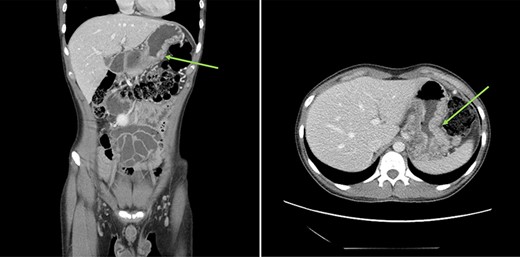

Urgent gastroscopy revealed a giant gastric ulcer in the antrum (Fig. 1) which was biopsied and sent for pathological investigation. The ulcer displayed no bleeding stigmata. He was started on eradication therapy for Helicobacter pylori. Pathology revealed a signet ring adenocarcinoma of the stomach (Fig. 2A and B). A computerized tomography (CT) scan (Fig. 3) showed a large mass in the distal stomach, and the ensuing positron emission tomography (PET) scan (Fig. 4) showed enlarged D1 perigastric lymph nodes with no obvious metastatic disease.

(A and B) PET scans (axial and coronal views) showing enlarged D1 perigastric lymph nodes (green arrows) and no apparent metastatic disease.